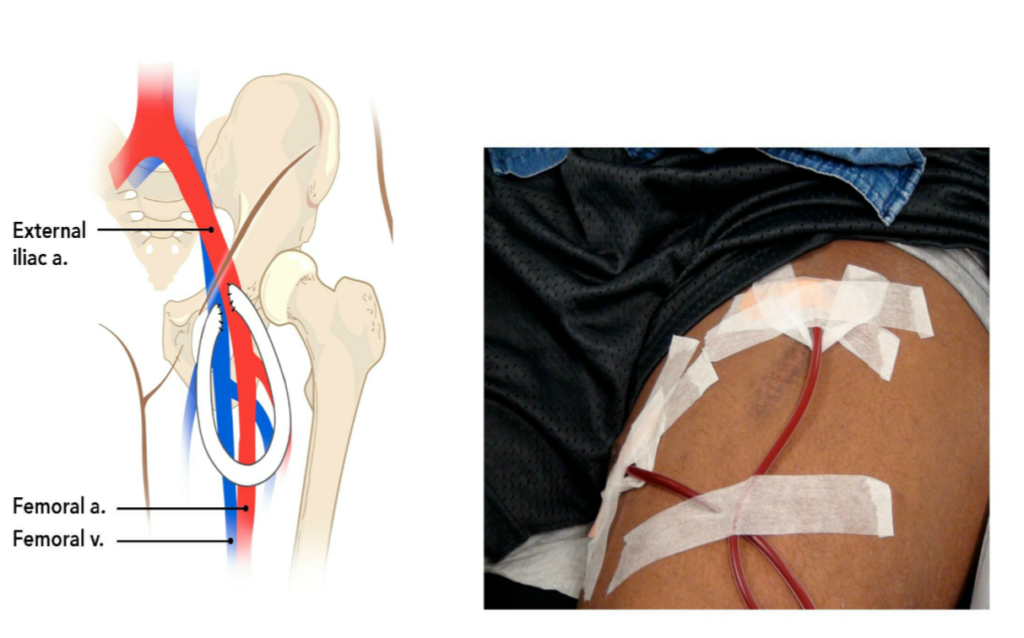

Thigh Graft